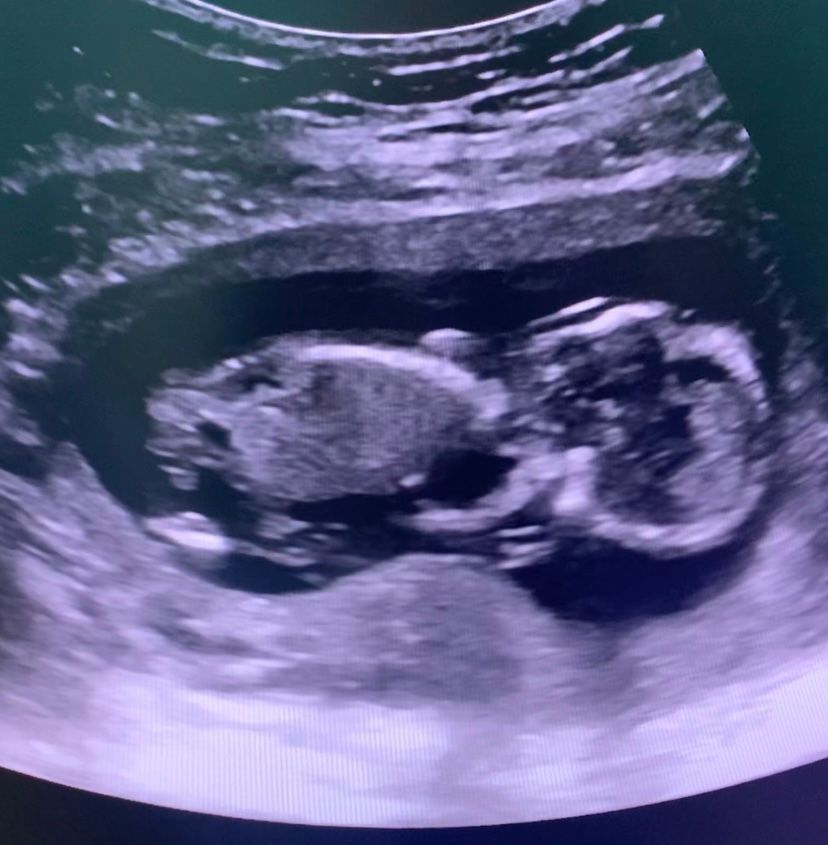

Эва, еще может быть узистка не айс поэтому не видит) не знаю почему но на последнем фото мне кажется я отчетливо вижу и носик и носовую кость

Солнце, вот и я кажется все вижу,может конечно потому,что хочу но уже хз,возможно она долго меня крутила и малыш говорит как-то неудобно лежит

У вас есть носовая косточка, я ее вижу. Уверена, у вас все хорошо

Family, 🙏вот и мне кажется я ее вижу,спасибо ❤️